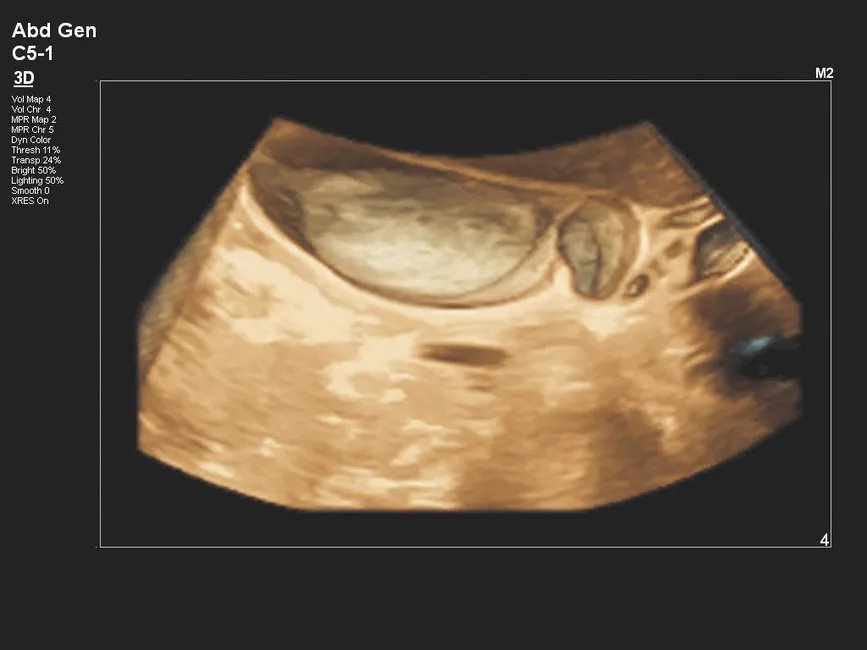

- Объемные режимы 3D/4D с технологиями визуализации типа TrueVue/FlexVue для повышения информативности акушерско-гинекологических и абдоминальных исследований.

| 3D/4D-режимы визуализации | Объемная и динамическая реконструкция анатомических структур для акушерско-гинекологических и абдоминальных исследований. |

| C5-1 | 1–5 | PureWave конвексный датчик | 160 | Абдоминальные исследования, акушерство, гинекология, исследования у пациентов с повышенным индексом массы тела |

| V9-2 | 2–9 | PureWave объемный конвексный датчик (3D/4D) | 192 | Объемные акушерско-гинекологические и абдоминальные исследования с 3D/4D-визуализацией |